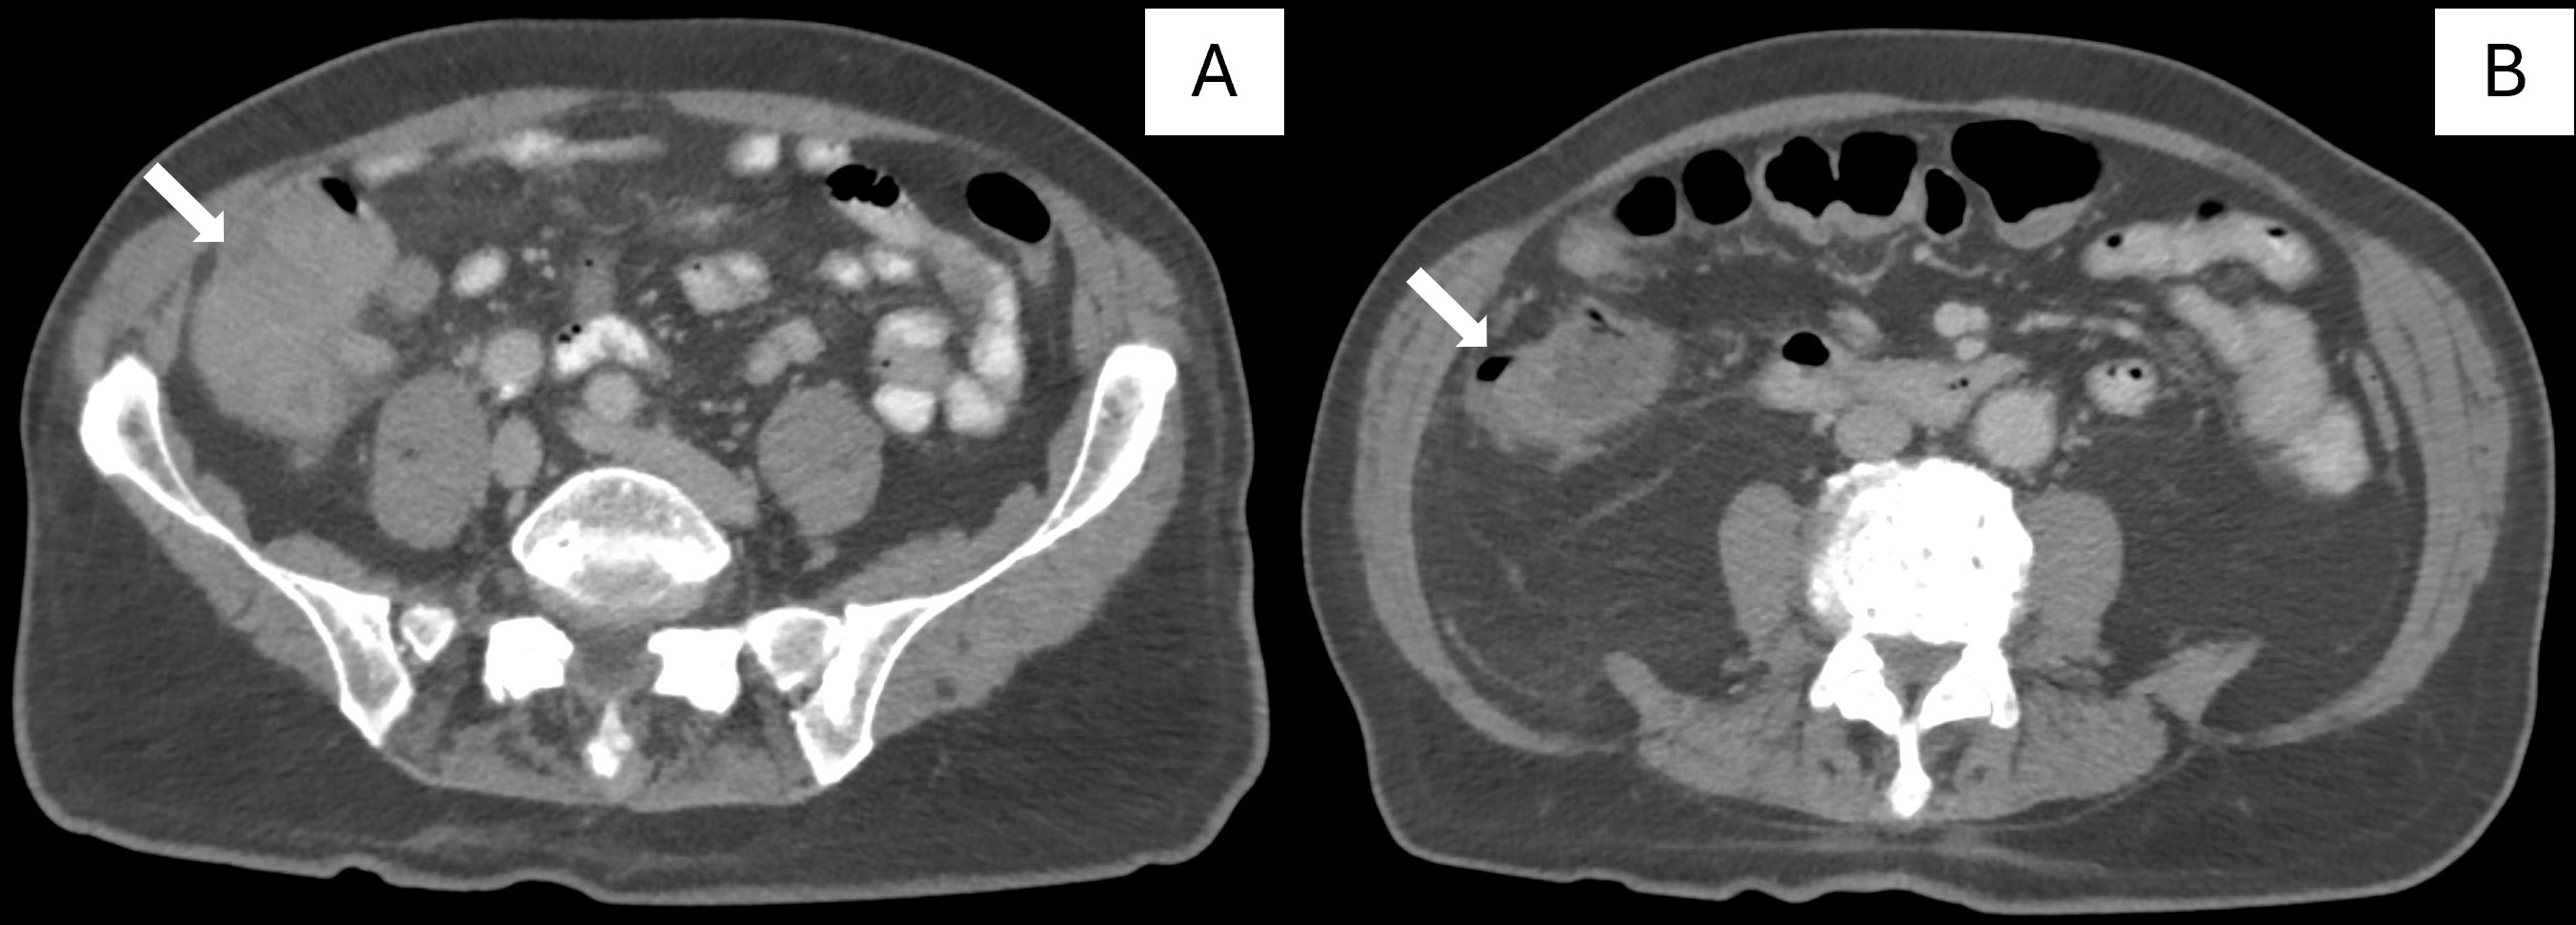

(A) Cecal squamous cell carcinoma and (B) Ascending colon adenocarcinoma.